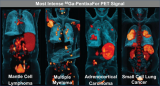

PET/MRI是一种有价值的治疗诊断技术

PET/MRI大约于12年前开发,即在单个扫描仪中结合了PET和MRI模态,近乎同时采集。这些扫描仪为临床医生提供了来自多参数MRI的详细解剖肿瘤评估,以及基于注射PET放射性示踪剂摄取的肿瘤的补充生理信息。 2023-06-16 PET/MRI